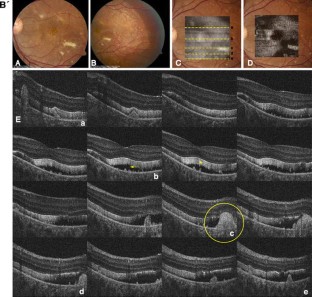

The objective of the paper is to study the retinal microstructure and function in a patient with autosomal recessive bestrophinopathy (ARB). Retinal function and morphology assessment in a patient diagnosed with a biallelic mutation in the BEST1 gene (heterozygote mutations: Leu88del17 and A195V) included: full-field electroretinogram (ffERG) and multifocal electroretinogram (mfERG), electro-oculogram (EOG) testing, and imaging with a high-resolution Fourier-domain optical coherence tomography (Fd-OCT) system (UC Davis Medical Center; axial resolution: 4.5 μm, acquisition speed: 9 frames/s, 1,000 A-scans/frame) combined with a flexible scanning head (Bioptigen Inc.). The 11-year old asymptomatic boy showed a well-demarcated retinopathy with deposits. Functional assessment revealed normal visual acuity, reduced central mfERG responses, delayed rod and rod-cone b-wave ffERG responses, and reduced light rise in the EOG. Fd-OCT demonstrated RPE deposits, photoreceptor detachment, elongated and thickened photoreceptor outer segments, but preserved inner retinal layers. In conclusion, ARB associated retinal dystrophy shows functional and morphological changes that overlap with classic Best disease. For the first time, high-resolution imaging provided in vivo evidence of RPE and photoreceptor involvement in ARB.

Fig. 1

Fig. 2

Fig. 3

Fig. 4